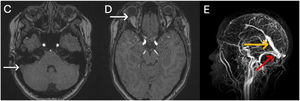

Durante la evaluación por el servicio de Medicina Interna Vascular, la paciente presentó un empeoramiento de la cefalea, acompañado de diplopía. Ante estos hallazgos, se realizó una resonancia magnética cerebral, que evidenció trombosis en el seno transverso derecho (fig. 2, panel C), aplanamiento posterior del globo ocular (fig. 2, panel D), engrosamiento de la vaina del nervio óptico y dilatación compensatoria del seno recto (fig. 2, panel E), hallazgos sugestivos de hipertensión intracraneana. Tras evaluar el riesgo-beneficio, se decidió no realizar manejo endovascular y se inició tratamiento con acetazolamida 250mg cada ocho horas, con posterior mejoría de los síntomas neurológicos.

Resonancia de cráneo: C) secuencia ponderada en T1 y supresión grasa: la flecha indica un realce anómalo que corresponde a una ocupación trombótica del seno transverso derecho. D) secuencia ponderada en T1 y supresión grasa: la flecha indica el aplanamiento posterior del globo ocular derecho. E) reconstrucción 3D del sistema venoso: la flecha naranja indica una dilatación compensatoria del seno transverso. La flecha roja indica un flujo filiforme a nivel seno transverso derecho.